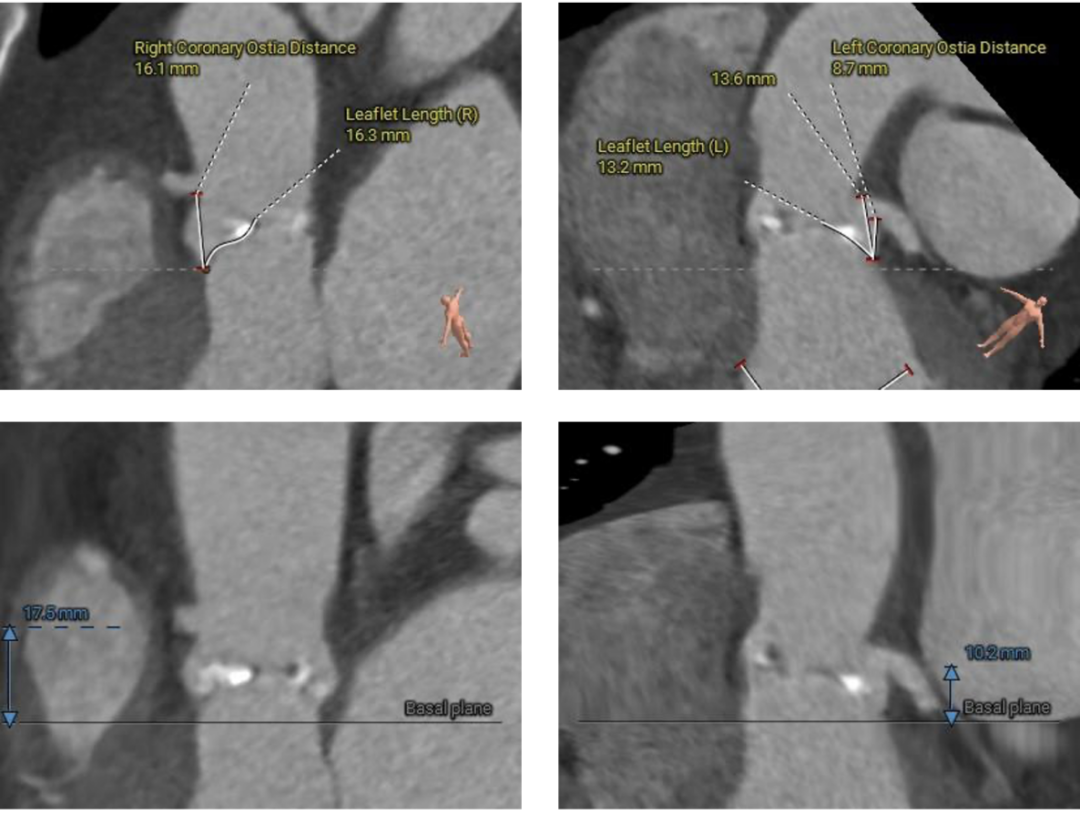

▲患者术前CT评估

▲主动脉根部测量

该病例主动脉根部结构较小,并且左冠脉开口高度距离瓣环较近,只有10.2mm,有一定的冠脉阻挡风险,手术团队讨论后决定在TAVR时进行冠脉保护,提前将冠脉通路准备好,并且结合球囊扩张及瓣膜释放工作位综合评估。

综合以上分析及病例特点,手术策略如下:三叶式主动脉瓣,轻度钙化伴瓣叶增厚,左冠开口较低,右冠高度可,综合瓦氏窦内径、窦管交界内径等因素考虑,左冠行冠脉保护,非横位心,弓距弓角可,左室内径可,双侧入路血管走形良好,整体入路血管条件可。计划使用20mm球囊预扩,预装23型号瓣膜,释放高度零位开始释放,最终依据术中情况决定是否做烟囱支架冠脉保护技术。